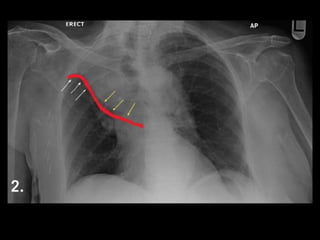

"Reverse S sign of Golden”

Golden S Sign